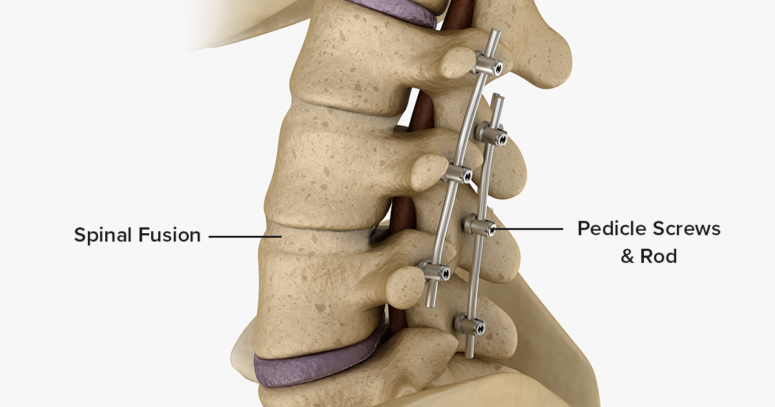

Spinal Fusion Spinal Surgery: Restoring Spinal Stability and Comfort

Spinal fusion is a surgical procedure used to join two or more vertebrae together permanently, eliminating motion between them. This helps in stabilizing the spine, relieving pain, and correcting deformities. The fusion process involves placing bone grafts or bone-like materials between the affected vertebrae, often supported by metal plates, screws, or rods.

Once fused, the vertebrae heal into a single solid bone, preventing movement that could irritate spinal nerves or cause further damage.

How the Procedure is Performed

Spinal fusion is performed under general anesthesia and typically lasts between 2 to 4 hours. Key steps include:

- Accessing the spine through an incision (from the front, side, or back)

- Removing the damaged disc or bone material

- Inserting bone grafts or synthetic substitutes

- Securing the area with screws, rods, or plates

- Closing the incision and applying dressings

Bone grafts may be taken from the patient’s own body (autograft), a donor (allograft), or synthetic substitutes.